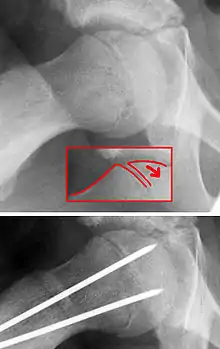

| X-ray showing a slipped capital femoral epiphysis, before and after surgical fixation. | |

The diagnosis requires x-rays of the pelvis, with anteriorposterior (AP) and frog-leg lateral views.[11] The appearance of the head of the femur in relation to the shaft likens that of a "melting ice cream cone", visible with Klein's line. The severity of the disease can be measured using the Southwick angle.

The disease can be treated with external in-situ pinning or open reduction and pinning. Consultation with an orthopaedic surgeon is necessary to repair this problem. Pinning the unaffected side prophylactically is not recommended for most patients, but may be appropriate if a second SCFE is very likely.[11]

Once SCFE is suspected, the patient should be non-weight bearing and remain on strict bed rest. In severe cases, after enough rest the patient may require physical therapy to regain strength and movement back to the leg. A SCFE is an orthopaedic emergency, as further slippage may result in occlusion of the blood supply and avascular necrosis (risk of 25 percent). Almost all cases require surgery, which usually involves the placement of one or two pins into the femoral head to prevent further slippage.[12] The recommended screw placement is in the center of the epiphysis and perpendicular to the physis.[13] Chances of a slippage occurring in the other hip are 20 percent within 18 months of diagnosis of the first slippage and consequently the opposite unaffected femur may also require pinning.

The risk of reducing this fracture includes the disruption of the blood supply to the bone. It has been shown in the past that attempts to correct the slippage by moving the head back into its correct position can cause the bone to die. Therefore the head of the femur is usually pinned 'as is'. A small incision is made in the outer side of the upper thigh and metal pins are placed through the femoral neck and into the head of the femur. A dressing covers the wound.